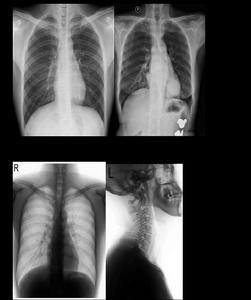

廣州醫學院港灣醫院醫院專業技術力量雄厚,設備先進,現有員工500餘人,專業技術人員占90%,其中高級職稱58人,中級職稱110人。擁有螺鏇CT、骨密度測量儀、全數位化X線機、彩色都卜勒心動超聲儀、全自動生化分析儀及ICU、CCU監護系統及世界先進的微創手術成套器械(包括

廣醫微創泌尿外科目前定編病床超過140張,有7間微創手術專用的層流手術室,及碎石中心、尿動力學檢查室、尿結石實驗室,擁有5000多萬臨床、教學及科研設備,包括尿流動力學檢查儀、紅外光譜分析儀、體外衝擊波碎石機、C臂X線機、膀胱鏡、輸尿管硬鏡、輸尿管軟鏡、微創腎鏡、腹腔鏡、前列腺電切鏡、鈥雷射、綠雷射、彈道碎石器及各種腔鏡培訓設備(腹腔鏡、輸尿管鏡、經皮腎鏡、前列腺電切鏡模擬訓練器等)。